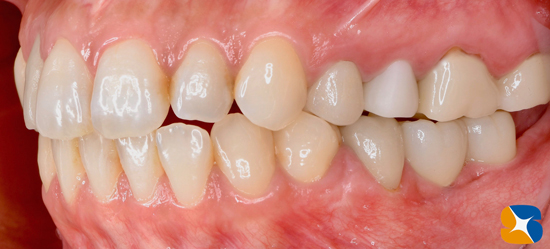

神戸市内から20代のモデル女性。主訴は「3年前に他院で入れたインプラントが痛くて噛めない。その事を訴えても『大丈夫。特に問題はありません。歯磨きが足りないのでは?』と言われるだけ。本当に大丈夫ですか?」

レントゲンで確認すると、かなり奥に傾いてインプラントが移植させていることが確認できます。

お口の中を拝見すると、かなり大きな被せ物がインプラントの支柱に接続されていることが伺えます。

そのため、歯茎も真っ赤に炎症しています。

このように異常に大きな被せ物を装着されてしまうと、なかなか上手くブラッシングは出来ません。